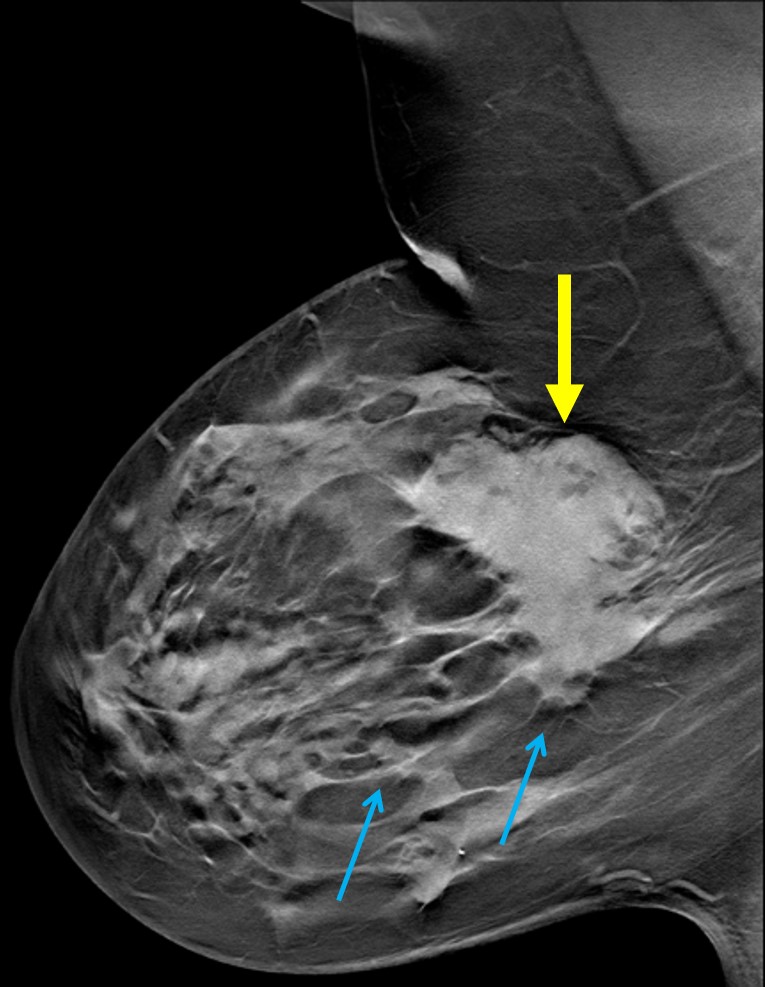

The most common cause of skin metastases in adult women is primary breast carcinoma, which comprises about 70% of cases [1]. Skin metastases have non-specific clinical appearances, making it challenging to differentiate them from other benign conditions [1]. We present a case of a 52-year-old female with type II diabetes and a three-month history of refractory skin lesions who did not respond to anti-inflammatory treatment. The patient subsequently complained of a right breast lump, evaluation of which led to the diagnosis of bilateral synchronous invasive lobular carcinoma.